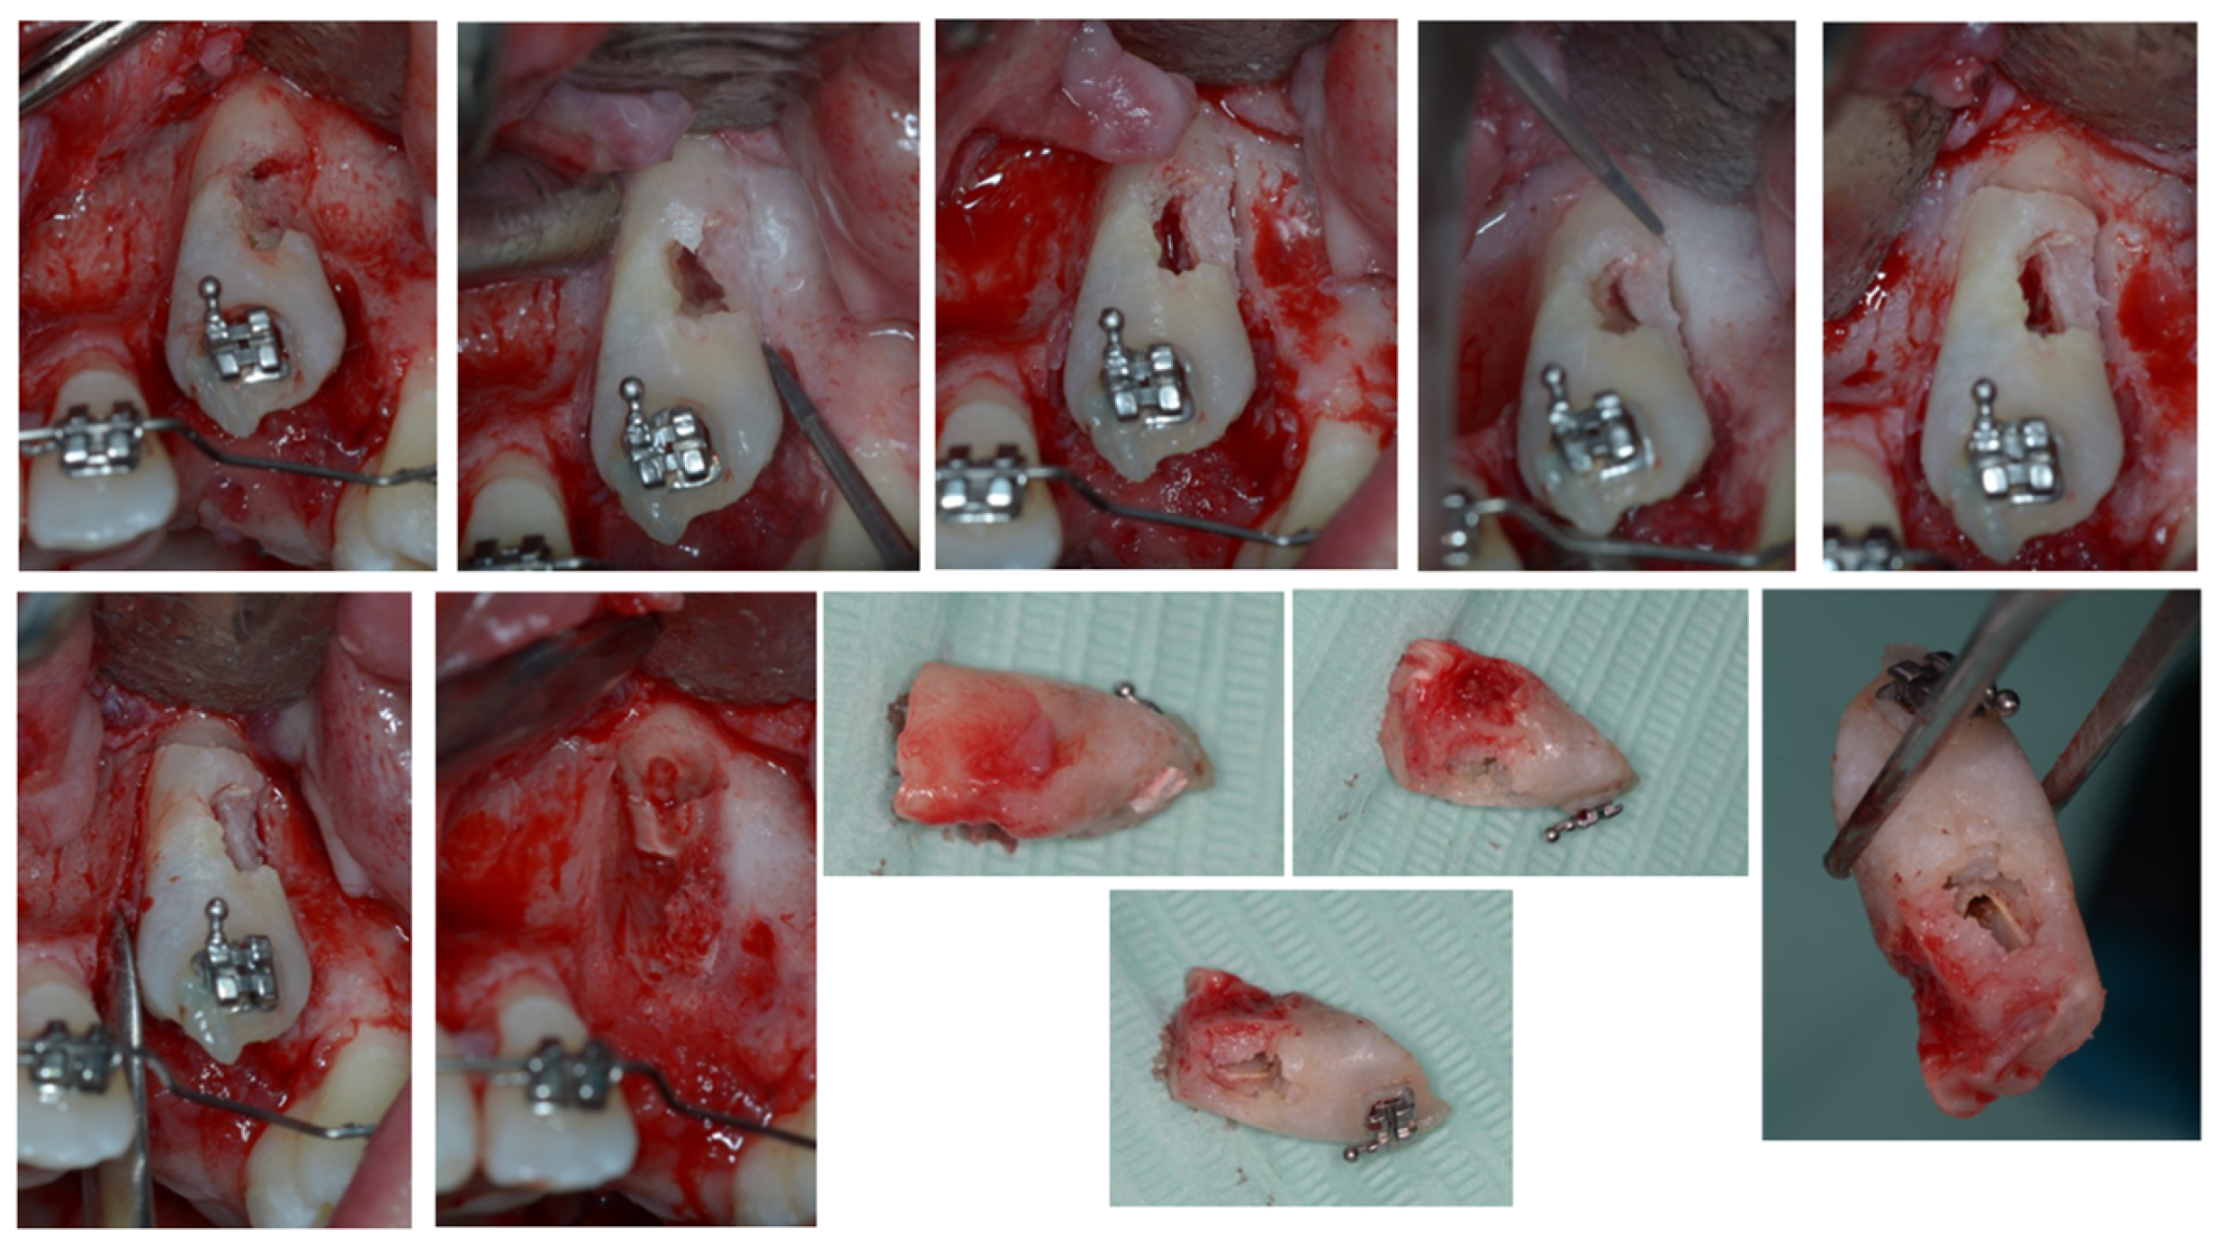

3. Therapeutic Interventions